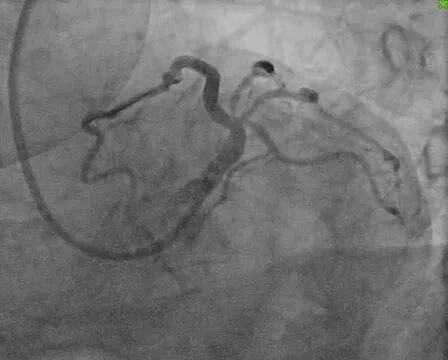

3. 对吻扩张:最终对吻球囊扩张,完美重建分叉部位血管解剖结构。

(术后多角度造影图像2)

整个手术历时4小时,术后IVUS确认支架贴壁良好,血流恢复理想,患者术后恢复顺利,次日即可下床活动,胸闷症状完全消失。